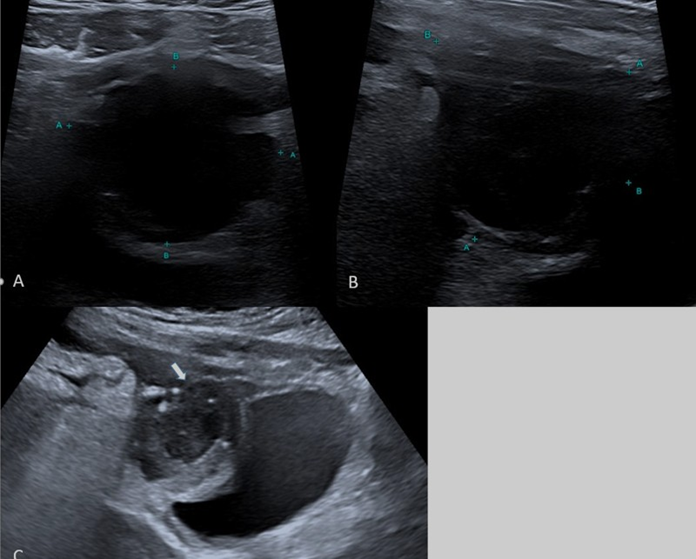

Ultrasonography (US) was performed to assess the pelvic region. The US findings indicated a heterogeneous collection of approximately 5 cm in diameter, which appeared to be connected with a subfascial-mesohypogastric urachal remnant. Additionally, marked hyperechogenicity was observed in the locoregional omental tissue (Figure 1).

Figure 1: Ultrasound - A,B) US with small parts (7,4-13 Mhz) probe shows supravesical cystic mass with irregularity of contours C) US with convex (3-8 MHz) probe shows the sopravescical cystic mass (white arrow) in communication with patent urachus (head white arrows) confirmed as a urachal cyst following image-guided aspiration.